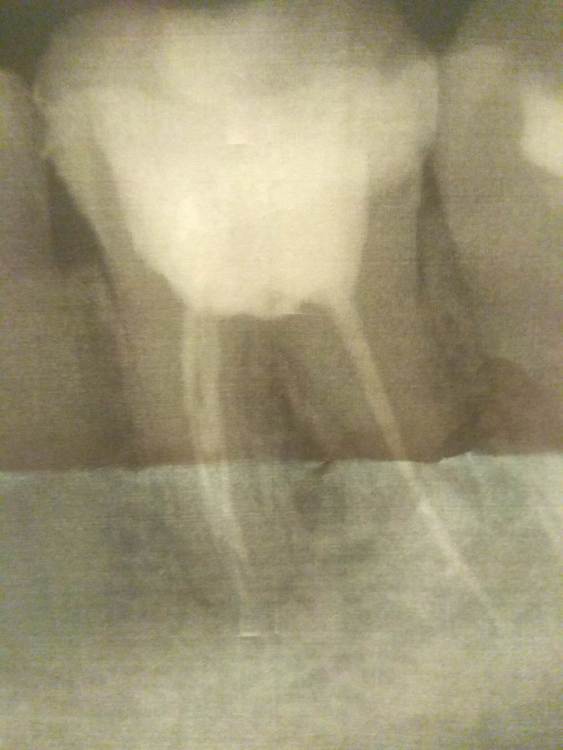

Primavera2023 Опубликовано 7 ноября, 2023 Автор Поделиться Опубликовано 7 ноября, 2023 (изменено) Боль при накусывании была всю неделю. Жевать с временной пломбой было невозможно. Также было немного больно сегодня при установке постоянной пломбы. После боль резко прошла. Надеюсь, ещё постоит. Штифт ставить не стали. Небольшой кариес (с которого началась боль) сбоку у десны (где пятый зуб) тоже оставили. Стоматолог сказала, что если убирать то зуб останется без стенки. И даже со штифтом держаться нормально не будет. На коронку денег нет, да и не хочу. Насколько критично, что так сделали? На депульпированном зубе кариес прогрессировать не будет? Вот снимок после лечения. Изменено 7 ноября, 2023 пользователем Primavera2023 Ссылка на комментарий

Carioznik Опубликовано 7 ноября, 2023 Поделиться Опубликовано 7 ноября, 2023 2 часа назад, Primavera2023 сказал: На депульпированном зубе кариес прогрессировать не будет? Будет. Ps: коронка нужна, судя по всему. Без коронки, да ещё и с кариесом (который будет прогрессировать постепенно) -зуб с высокой степенью вероятности "раскрошится" в течении нескольких лет и его придется, скорее всего, удалить . 1 Ссылка на комментарий